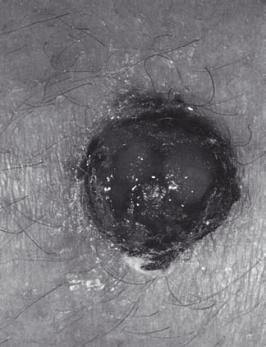

5.3  Melanoma maligno

Melanoma it.Wikipedia Melanoma salutedonna

Noduli molli scuri circondati da una zona di pelle infiammata (arrossata). Metastasi.

Melanoma iniziale

Melanoma maligno noduloso

Segni sospetti: